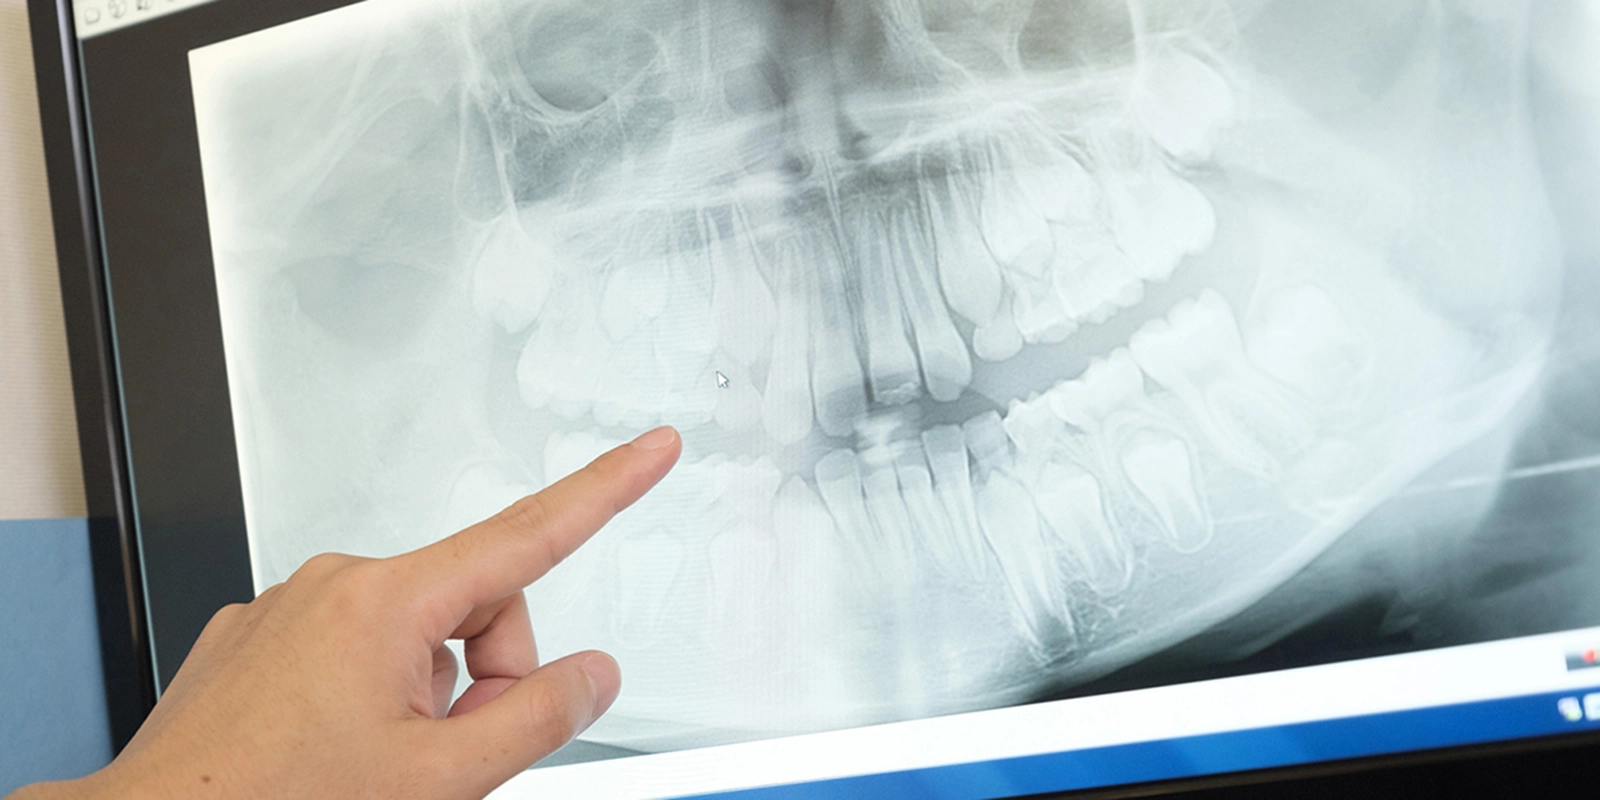

さらに、治療中の映像を記録・保存できる機能により、治療前後の状態を患者さんにも分かりやすく説明することができます。